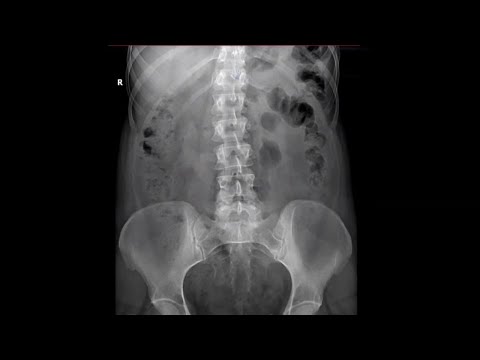

Укладка при внутривенной экскреторной урографии